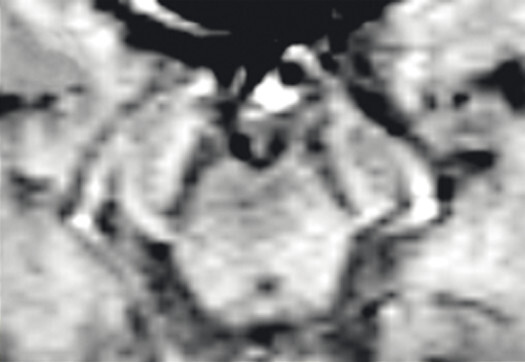

- Der Nachweis der Degeneration des dopaminproduzierenden Nigrosoms 1 innerhalb der Substantia nigra und des damit verbundenen Verlusts des Schwalbenschwanzzeichens (Swallow Tail Sign; Abb. 69.2) zeigt keinen eindeutigen Mehrwert in Bezug auf Diagnose und Differenzialdiagnose von Parkinson-Syndromen. Die Beurteilung des Schwalbenschwanzzeichens ist nämlich deutlich scanner- und befunderabhängig und wird in bis zu 50% der Fälle auch bei Patientinnen und Patienten mit frontotemporaler Demenz und Alzheimer-Demenz als anomal eingestuft [12].

Abb. 69.2 Parkinson-Syndrome.

a Schwalbenschwanzzeichen beidseits als Ausdruck eines unauffälligen dopaminproduzierenden Nigrosoms 1 (Pfeile).

b Beim idiopathischen Parkinson-Syndrom, aber auch bei anderen neurodegenerativen Erkrankungen, ist das Schwalbenschwanzzeichen (Swallow Tail Sign) in der SWI-MRT (Schichtdicke 2 mm) einseitig oder beidseitig nicht abgrenzbar (Pfeile).